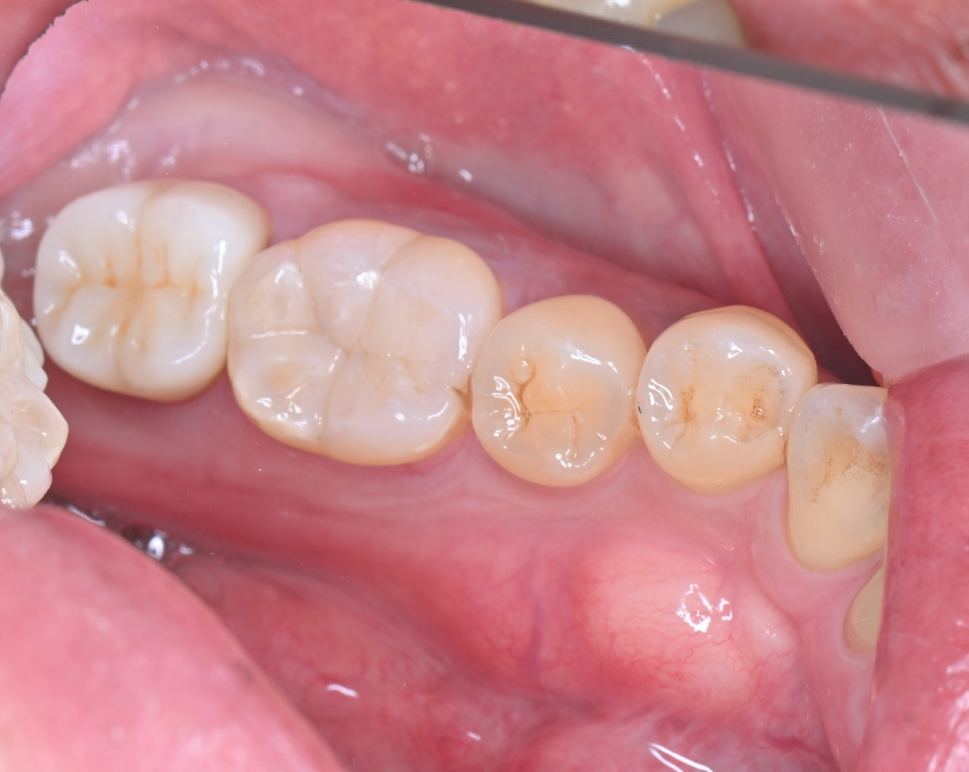

材料を丁寧に詰め、完成した状態がこちらです。

こちらの方は他の所にも銀歯がはいっており、治療が進むにつれ綺麗になり嬉しい!とお喜びいただきました。ダイレクトボンディングは長持ちしやすい治療ですが、強くかみ合わせる習慣がある方には別の症例をご提案することもあります。

After